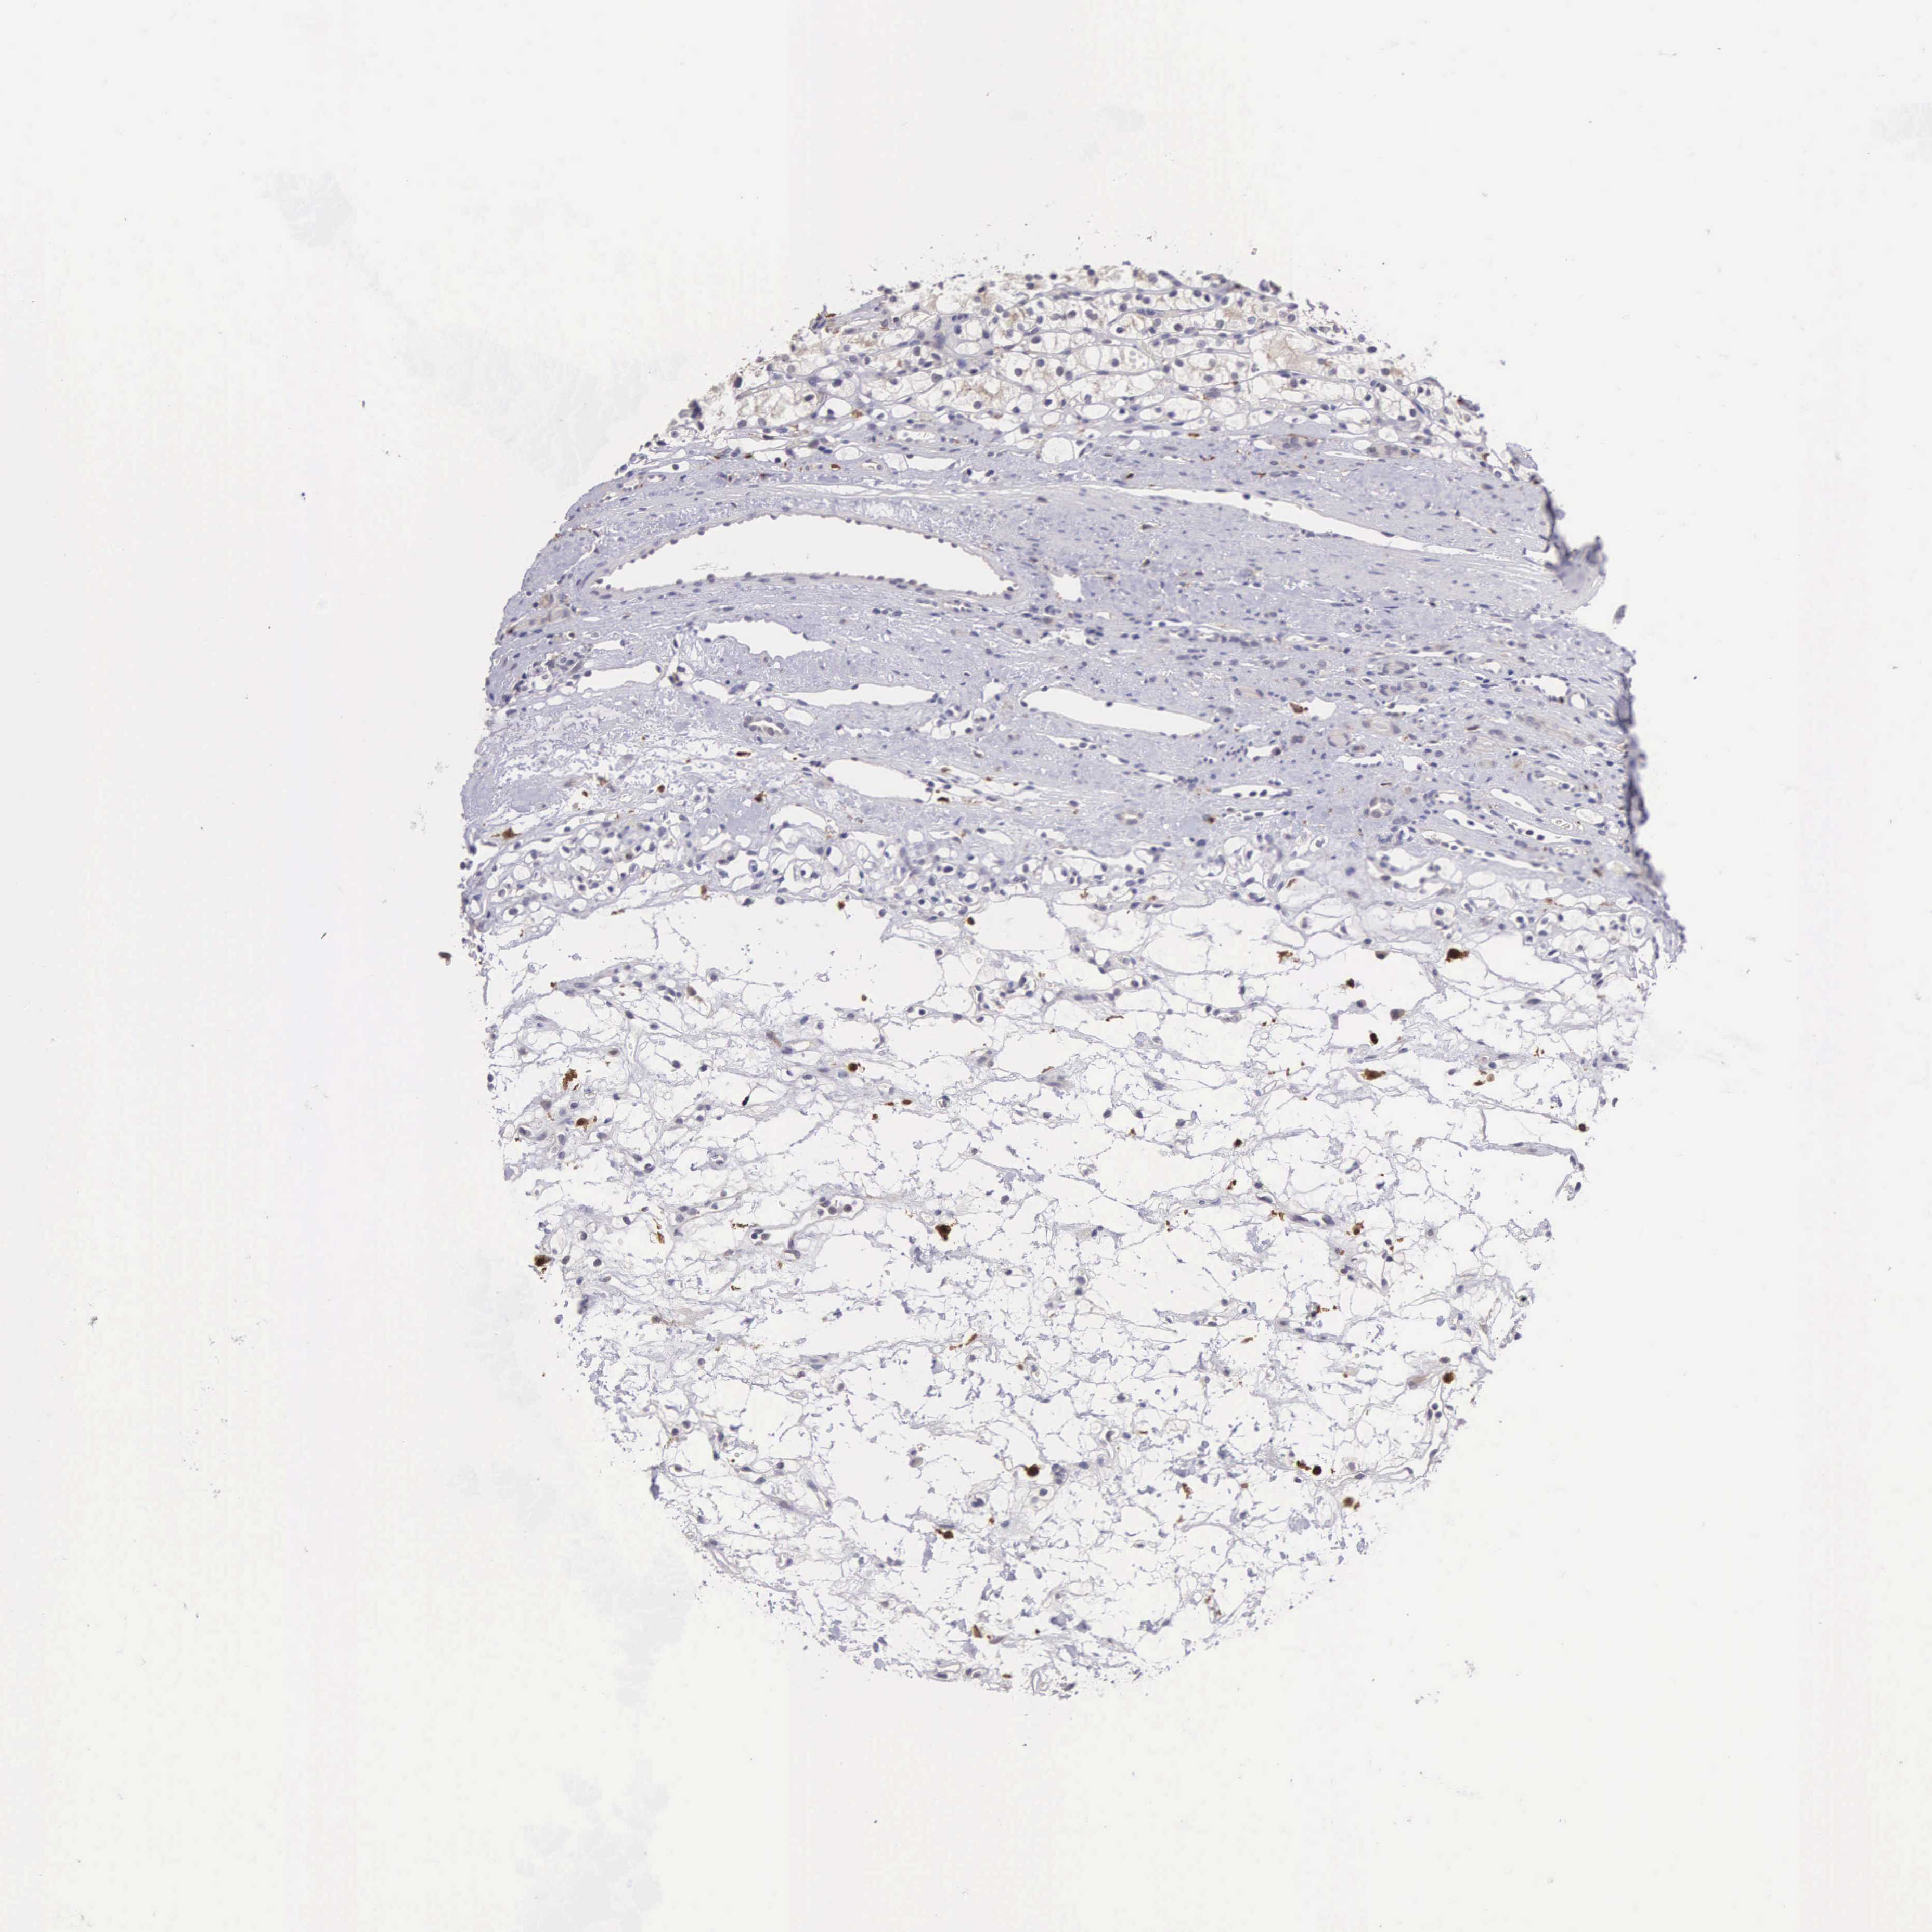

KIDNEY RENAL CLEAR CELL CARCINOMA (VALIDATION) - Interactive survival scatter ploti

The Survival Scatter plot shows the clinical status (i.e. dead or alive) for all individuals in the patient cohort, based on the same data that underlies the corresponding Kaplan-Meier plots. Patients that are alive at last time for follow-up are shown in blue and patients who have died during the study are shown in red.

The x-axis shows the expression levels (FPKM) of the investigated gene in the tumor tissue at the time of diagnosis. The y-axis shows the follow-up time after diagnosis (years). Both axes are complimented with kernel density curves demonstrating the data density over the axes. The top density plot shows the expression levels (FPKM) distribution among dead (red) and alive patients (blue). The right density plot shows the data density of the survived years of dead patients with high and low expression levels respectively, stratified using the cutoff indicated by the vertical dashed line through the Survival Scatter plot. This cutoff is automatically defined based on the FPKM cutoff that minimizes the p-score. The cutoff can be changed by dragging the vertical line or by entering a cutoff value in the square labeled "Current cut-off".

Under the Survival Scatter plot the p-score landscape (black curve; left axis) is shown together with dead median separation (red curve; right axis). Dead median separation is the difference in median mRNA expression between patients who have died with high and low expression, respectively. It is calculated as follows: median FPKM expression of dead patients with high expression - median FPKM expression of dead patients with low expression. This is intended to aid the user in visually exploring custom cutoffs and the associated p-scores and dead median separation.

Individual patient data is displayed and can be filtered by clicking on one or more of the category buttons on the top of the page. Categories describing expression level and patient information include: high, low, alive, dead, female, male and tumor stages. The scale of the x-axis can be toggled between linear and log-scale by clicking on the "x log" button. Mouse-over function shows TCGA ID, patient information and mRNA expression (FPKM) for each patient.

& Survival analysisi

Kaplan-Meier plots summarize results from analysis of correlation between mRNA expression level and patient survival. Patients were divided based on level of expression into one of the two groups "low" (under cut off) or "high" (over cut off). X-axis shows time for survival (years) and y-axis shows the probability of survival, where 1.0 corresponds to 100 percent.

CDC45 is validated prognostic, high expression is unfavorable in Kidney Renal Clear Cell Carcinoma (validation)

: 3.03

Average pTPM 2.3

Number of samples 100